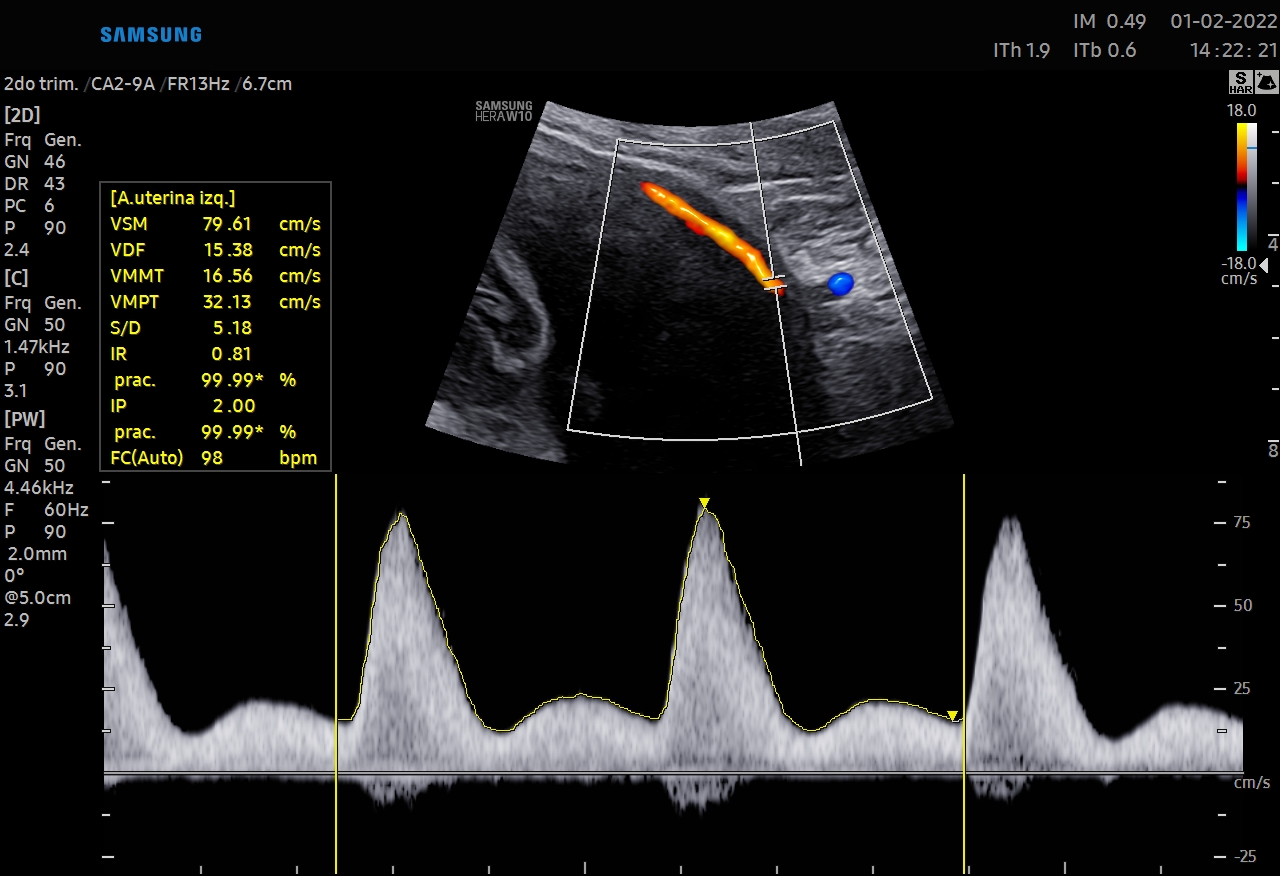

Doppler de Arterias Uterinas

Leer más